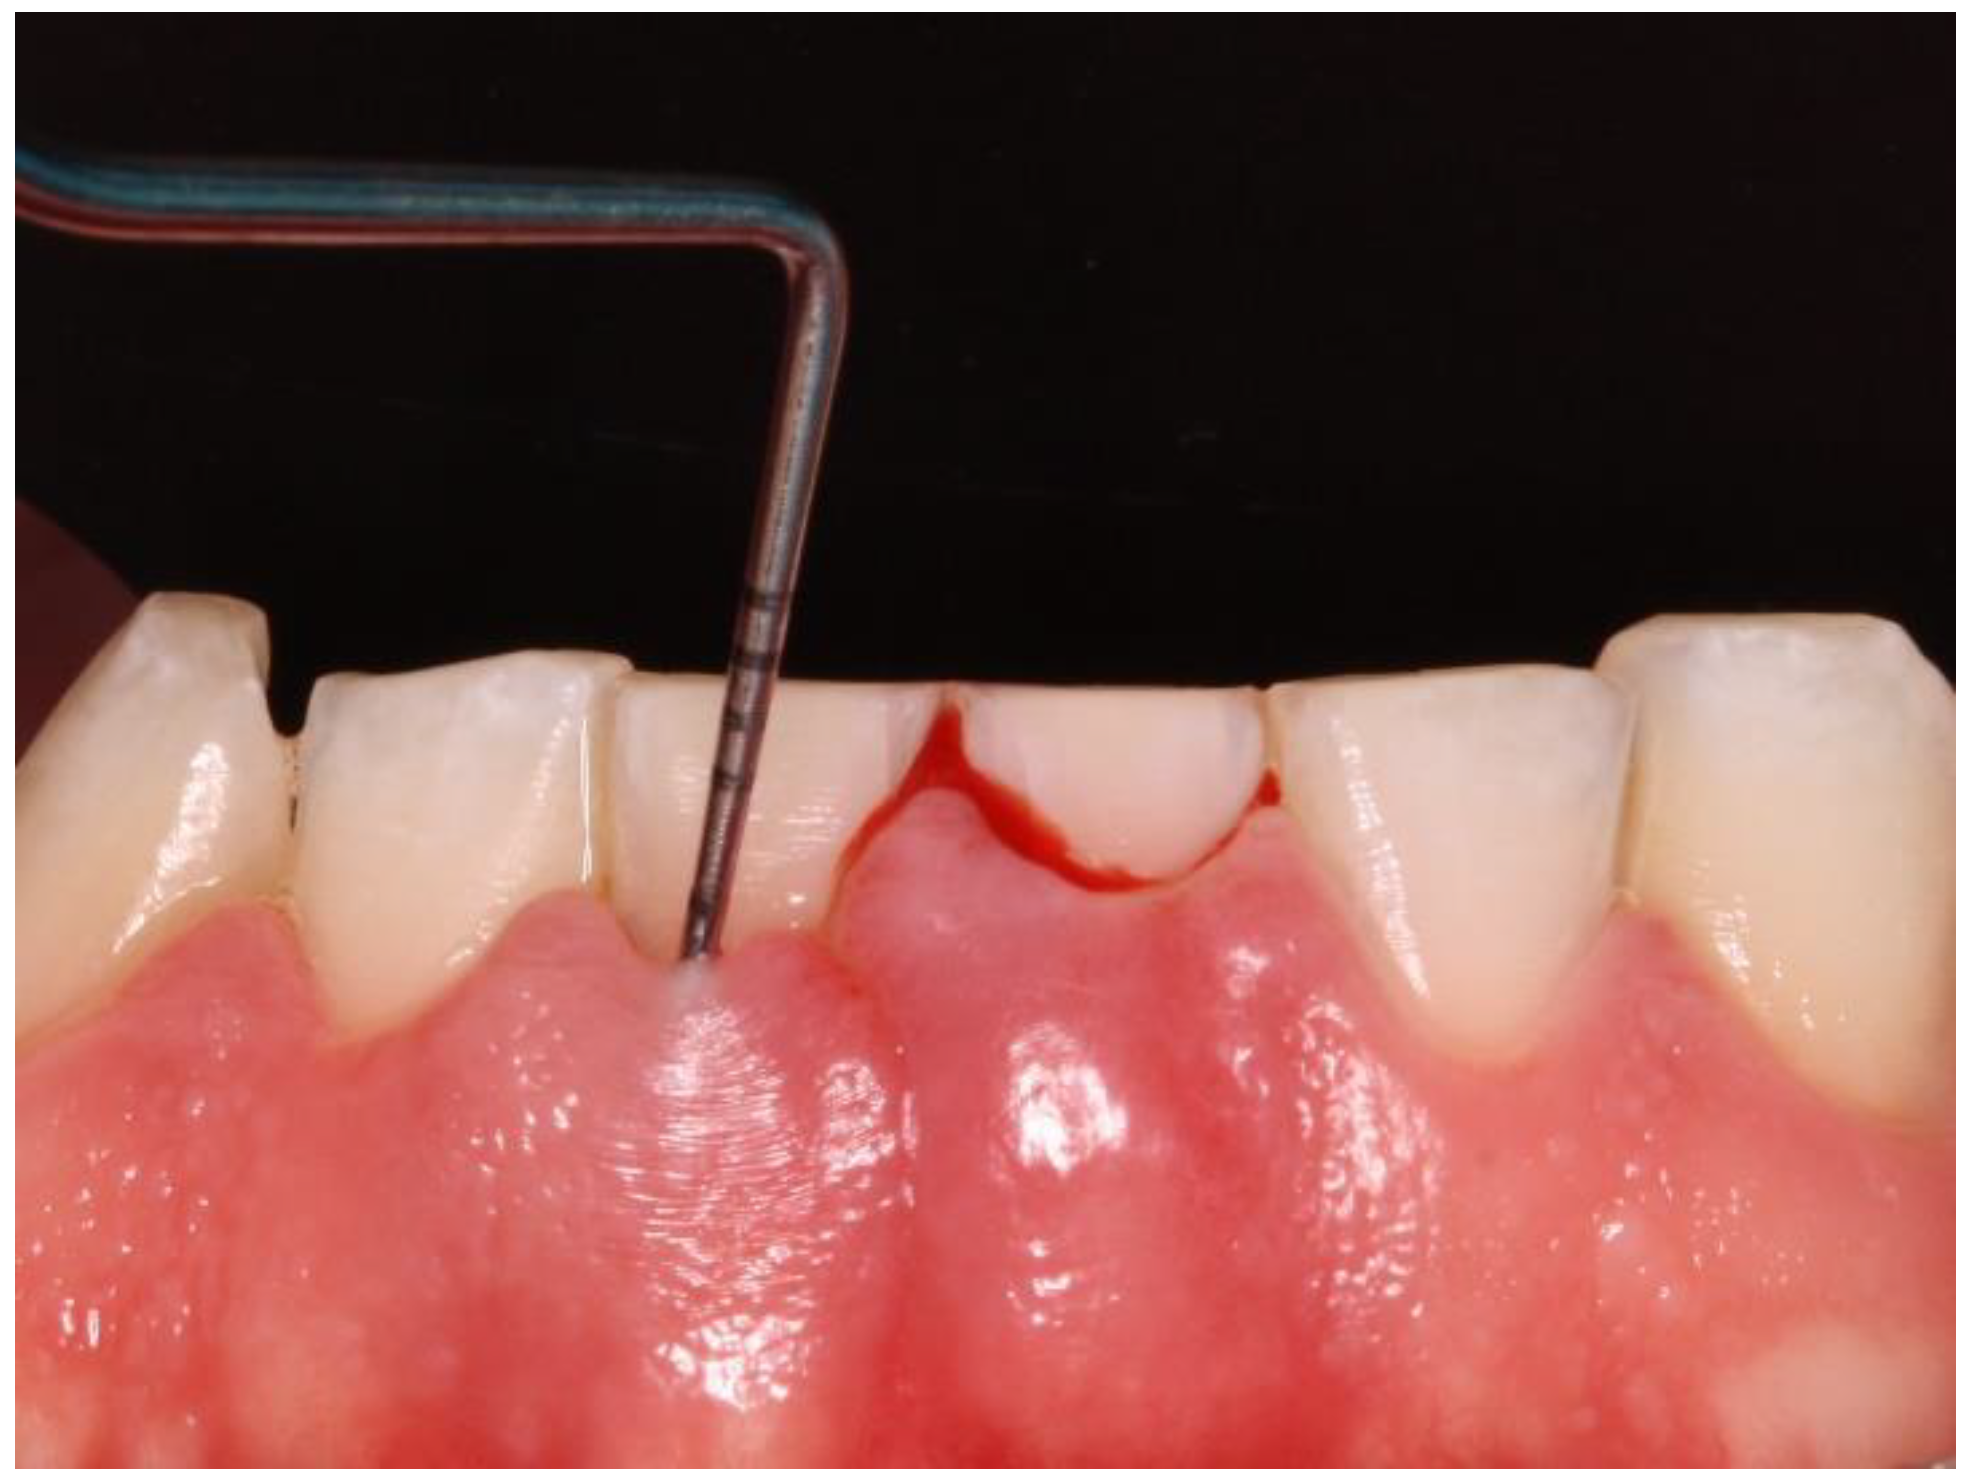

Clinical data of all teeth, excluding third molars, were obtained during oral examinations at initial visits. Accredited Oral Hygienists and Dentists performed whole-mouth oral examinations. The manual periodontal probe PCPUNC15 was used for oral examinations. Oral examinations included periodontal pocket depth (PPD; 6 sites per tooth) (Figure 1) and bleeding on probing (GBI; 4 sites per tooth).[23]

The Gingival Bleeding Index (GBI) was performed to assess the presence or absence of gingival inflammation. Bleeding areas were determined by running the periodontal probe over four points per tooth (mesial, distal, buccal, and lingual). (Figure 2) The calculation to obtain the percentage value was as follows: number of bleeding sites/number of evaluated sites x 100.

Figure 2. Bleeding after periodontal probing.